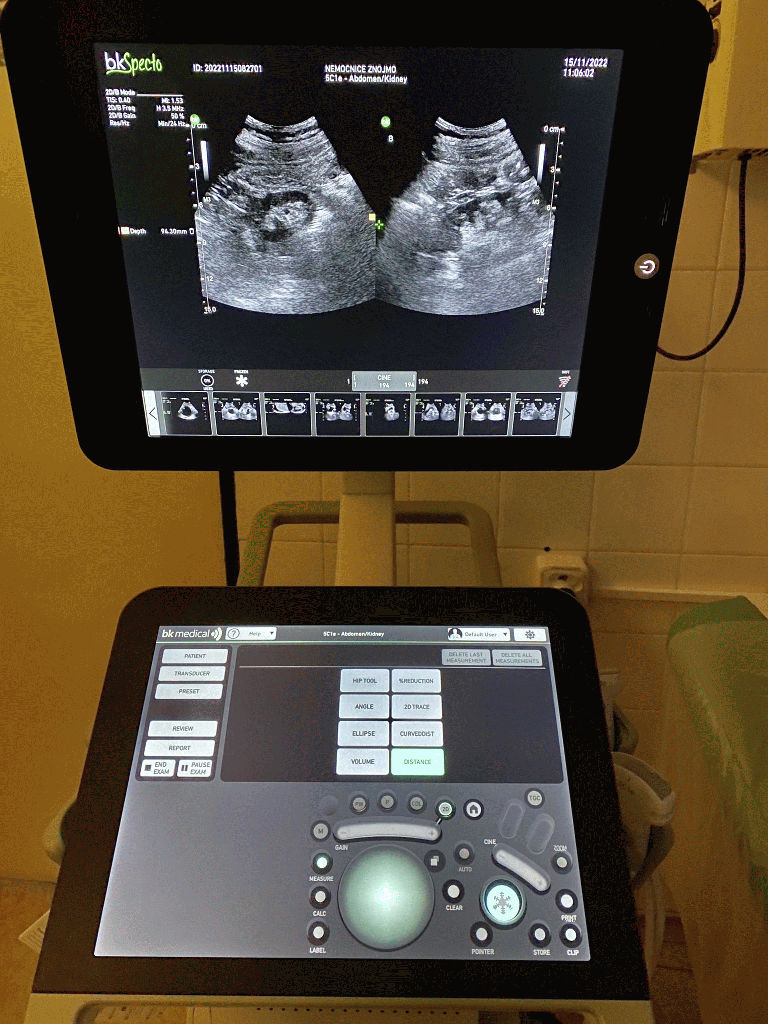

V současné době není v České republice zaveden systematický program časné detekce karcinomu prostaty. Cílem pilotního programu je využít jednoduchý, levný a dostupný marker – PSA, který se může použít pro rozhodnutí o indikaci k dalšímu došetření, případně biopsii, a eliminovat přechod karcinomu do již klinicky rozvinutého stadia, nastavit a vyhodnotit navržené postupy pro časný záchyt. „Prognóza pacienta závisí na včasné diagnóze, protože lokalizované onemocnění lze radikálně léčit. Proto jsme pořídili speciální ultrazvuk pro Urologické oddělení, díky kterému mohli naši urologové letos na jaře zavést nejmodernější metodu pro zachycení zhoubných nádorů prostaty – fúzní punkční biopsii prostaty. Včasný záchyt detekce karcinomu prostaty byl také důvod, proč jsme se do pilotního programu přihlásili “ uvedl ředitel Nemocnice Znojmo Martin Pavlík, Nemocnice Znojmo je ve zpracování odebraných vzorků soběstačná. Vzorky PSA z krve jsou zpracovány na Oddělení klinické biochemie. Vzorky z biopsie zpracovává Patologicko-anatomické oddělení.